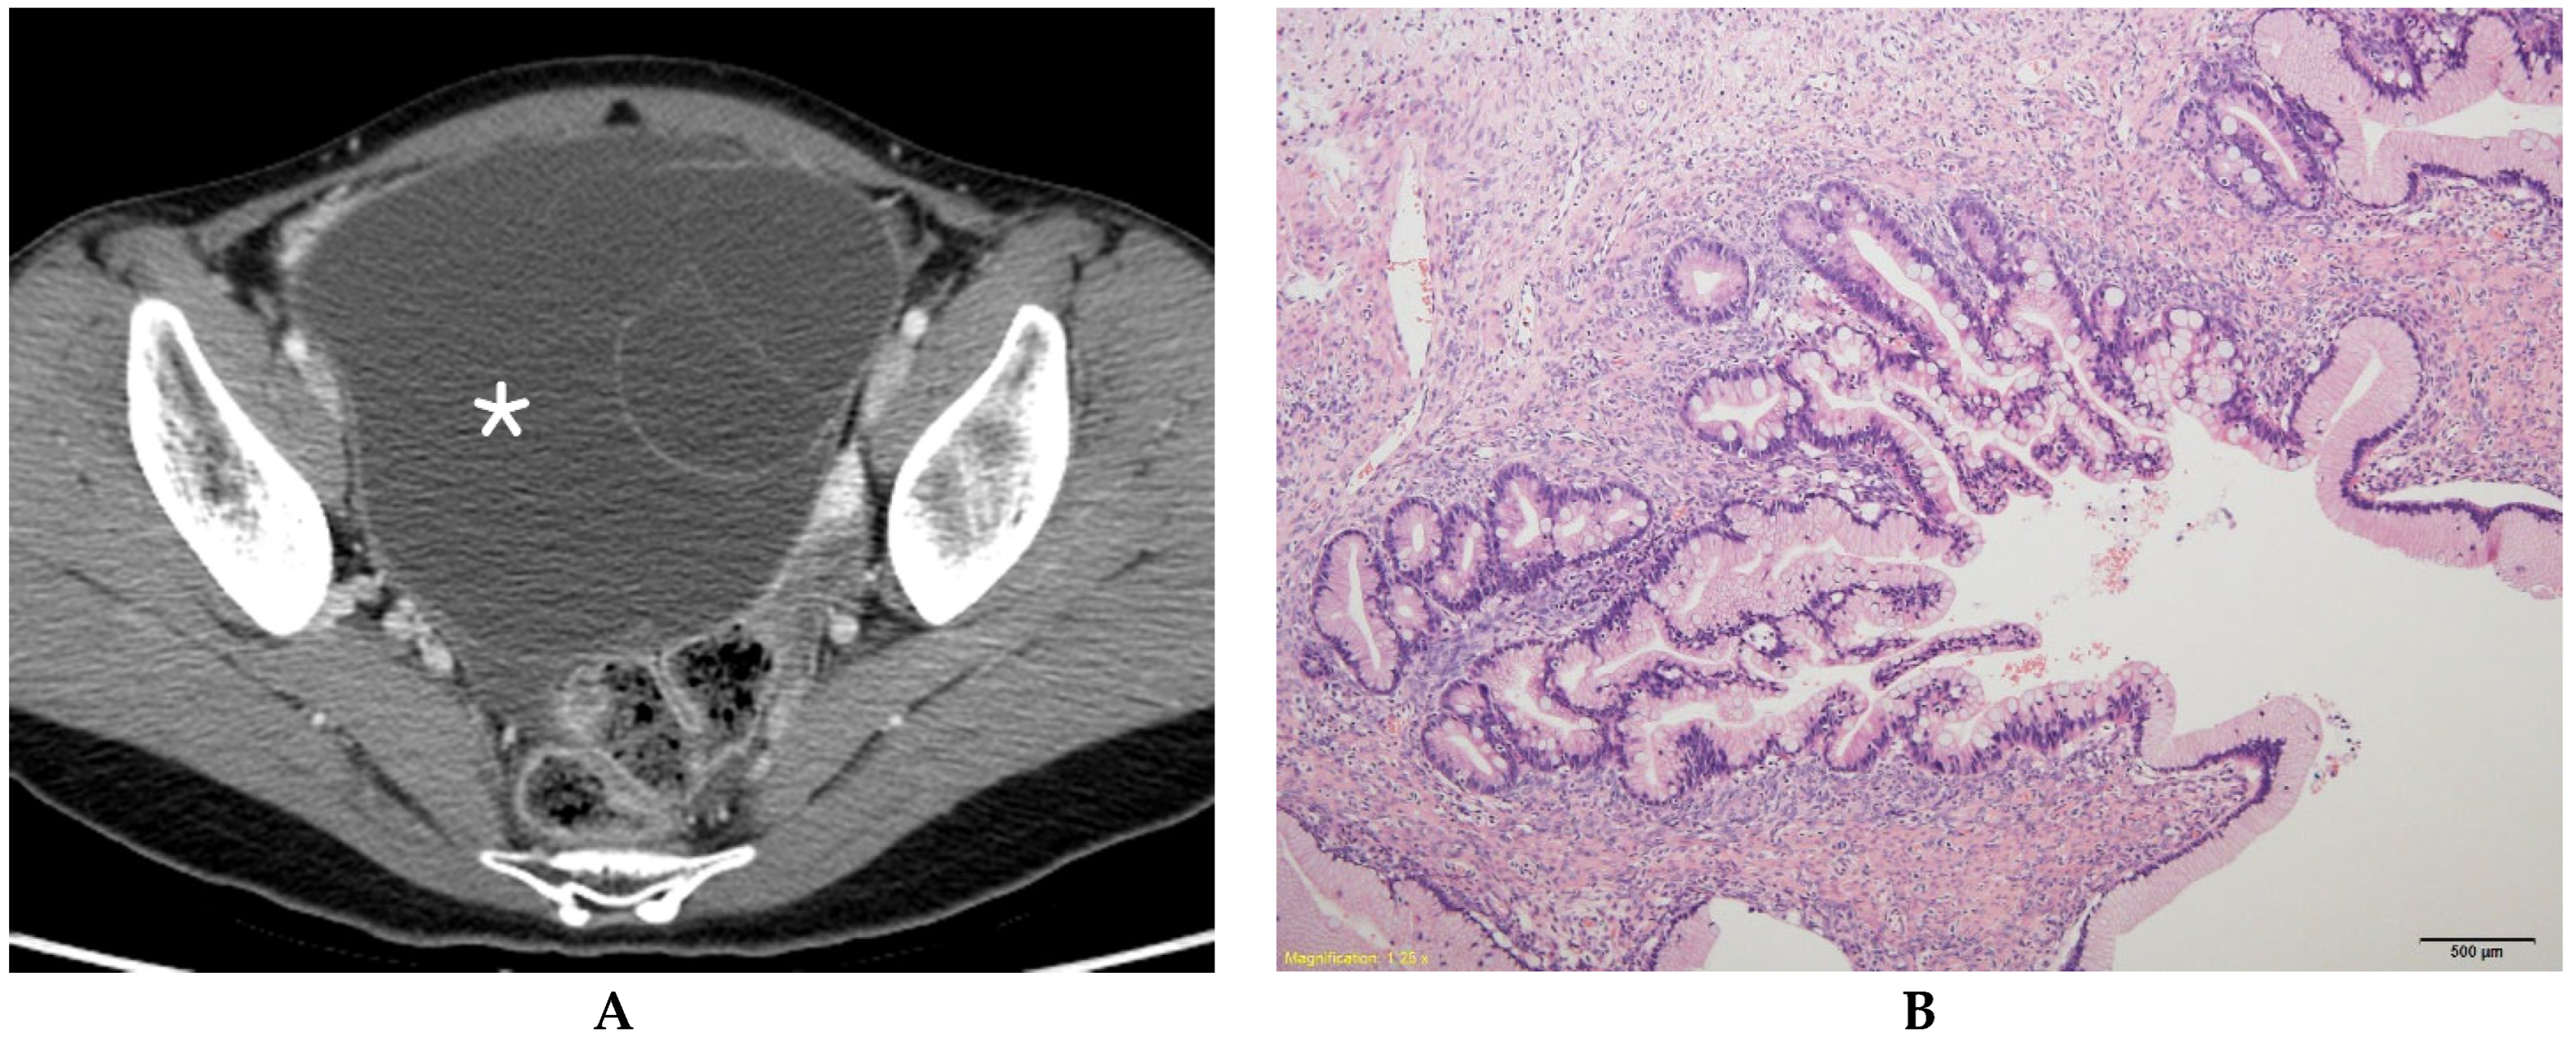

Figure 1.

Mucinous borderline ovarian tumor in a 31-year-old woman. (A) Contrast-enhanced axial CT shows a multilocular cystic mass (*) without a solid component in the right ovary. (B) A histologic section shows aggregates of small loculi covered by a complex mucinous epithelium with a villous architecture (hematoxylin and eosin 100×).